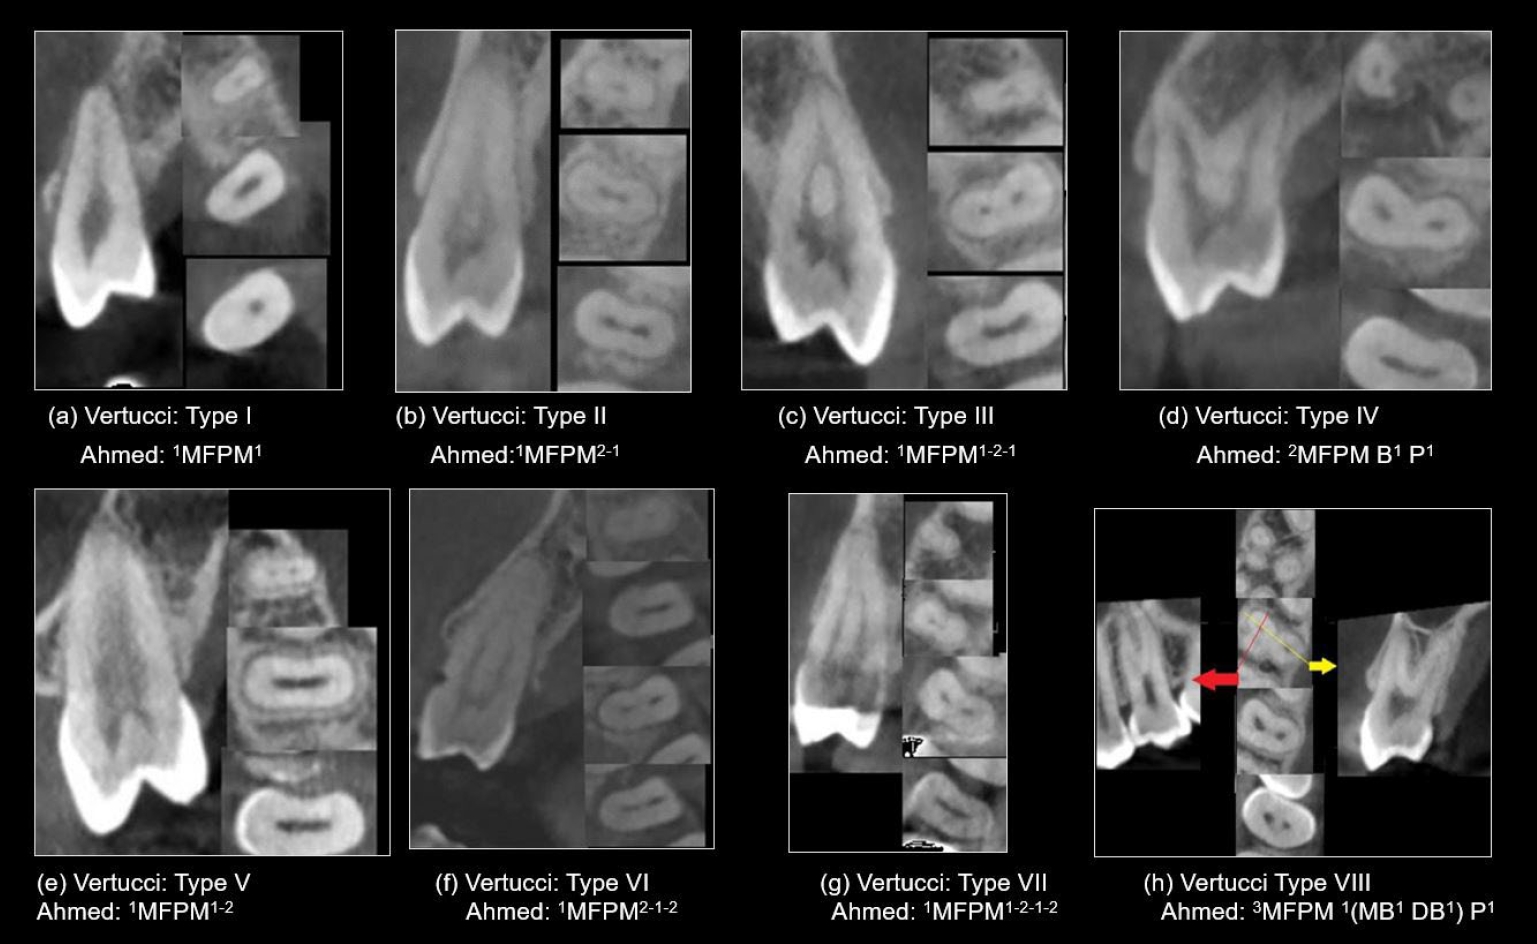

The CBCT scans were analyzed independently by two specialists with 15 years of clinical experience, who were calibrated prior to the assessment using 20 CBCT scans of maxillary premolar teeth showing root canal morphology according to the Vertucci’s and Ahmed’s classification systems (Figure 1). Inter- and intra-examiner reliability was assessed with a 3-week interval between the first and second assessments. Disagreements were resolved through open discussion and a consensus-based approach.

Figure 1.

Representative cone-beam computed tomography images in sagittal and axial views (apical, middle, coronal), showcasing various root canal system configurations in maxillary first premolars (MFPM) based on Vertucci’s and Ahmed’s classifications.

Figure 1. Representative cone-beam computed tomography images in sagittal and axial views (apical, middle, coronal), showcasing various root canal system configurations in maxillary first premolars (MFPM) based on Vertucci’s and Ahmed’s classifications.